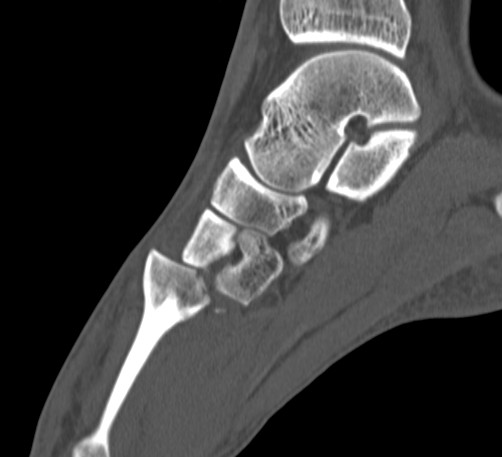

CT scan

Dorsal displacement of metatarsals

Compression fractures / nutcracker of cuboid